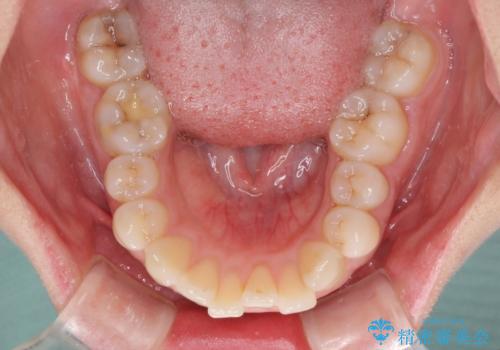

- 前歯のデコボコを気にして来院された患者様です。

当初は口元の突出感はあまり気にされていない様子だったので、インビザラインによる非抜歯矯正をお勧めしたが、ふっくらとした口元を改善したいとのことで、積極的に口元の突出感を改善することとしました。

上下左右第一小臼歯4本の抜歯を行い、ワイヤー装置による矯正治療を行うこととしました。